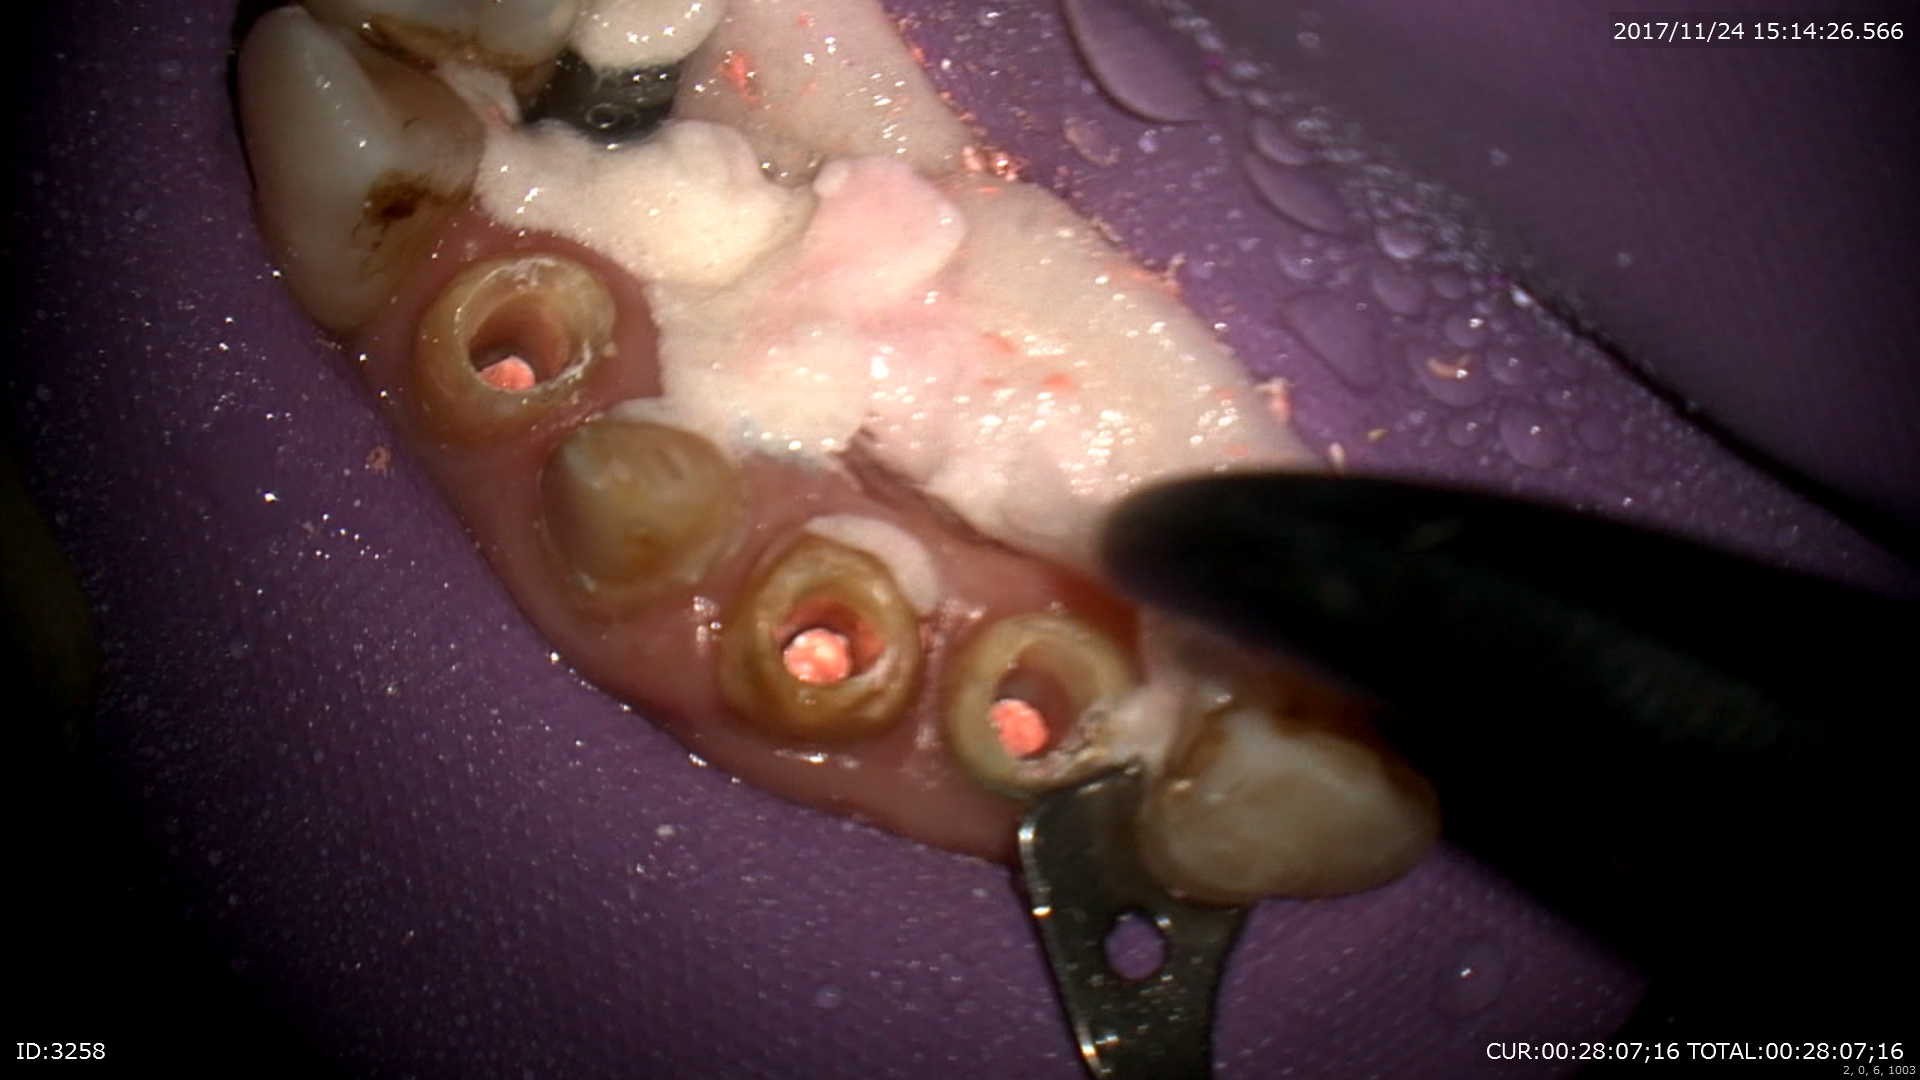

マイクロエンド

今日は2回目

右が前回左は本日

綺麗になりました。

2回目で治療が終わりました。根管充填。